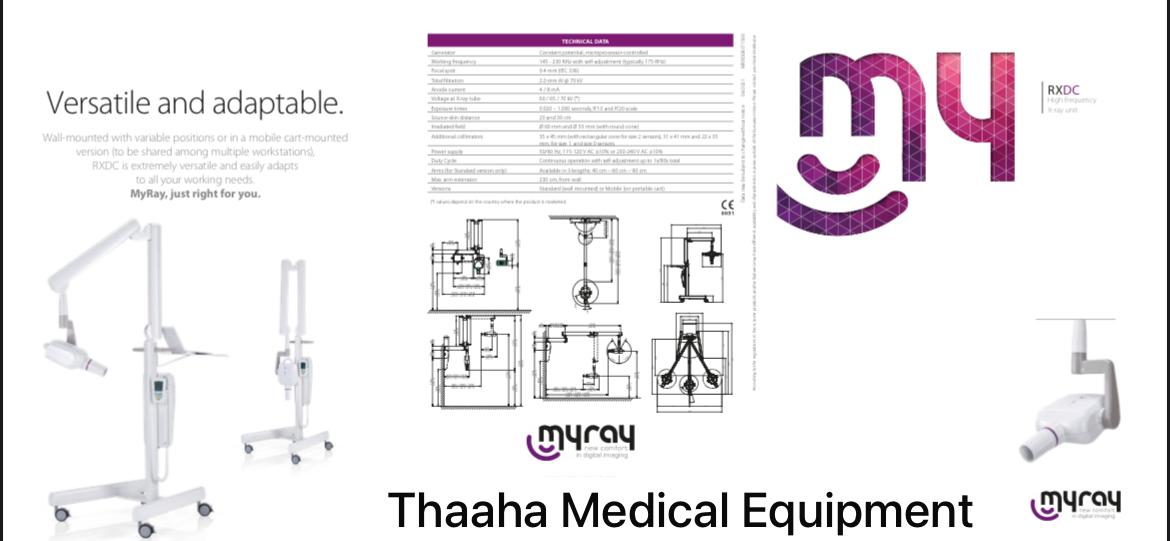

DENTAL X RAY - MOBILE - MYRAY ITALIAN

DENTAL X RAY - MOBILE - MYRAY ITALIAN

MOBILE DENTAL XRAY

MOBILE DENTAL XRAY